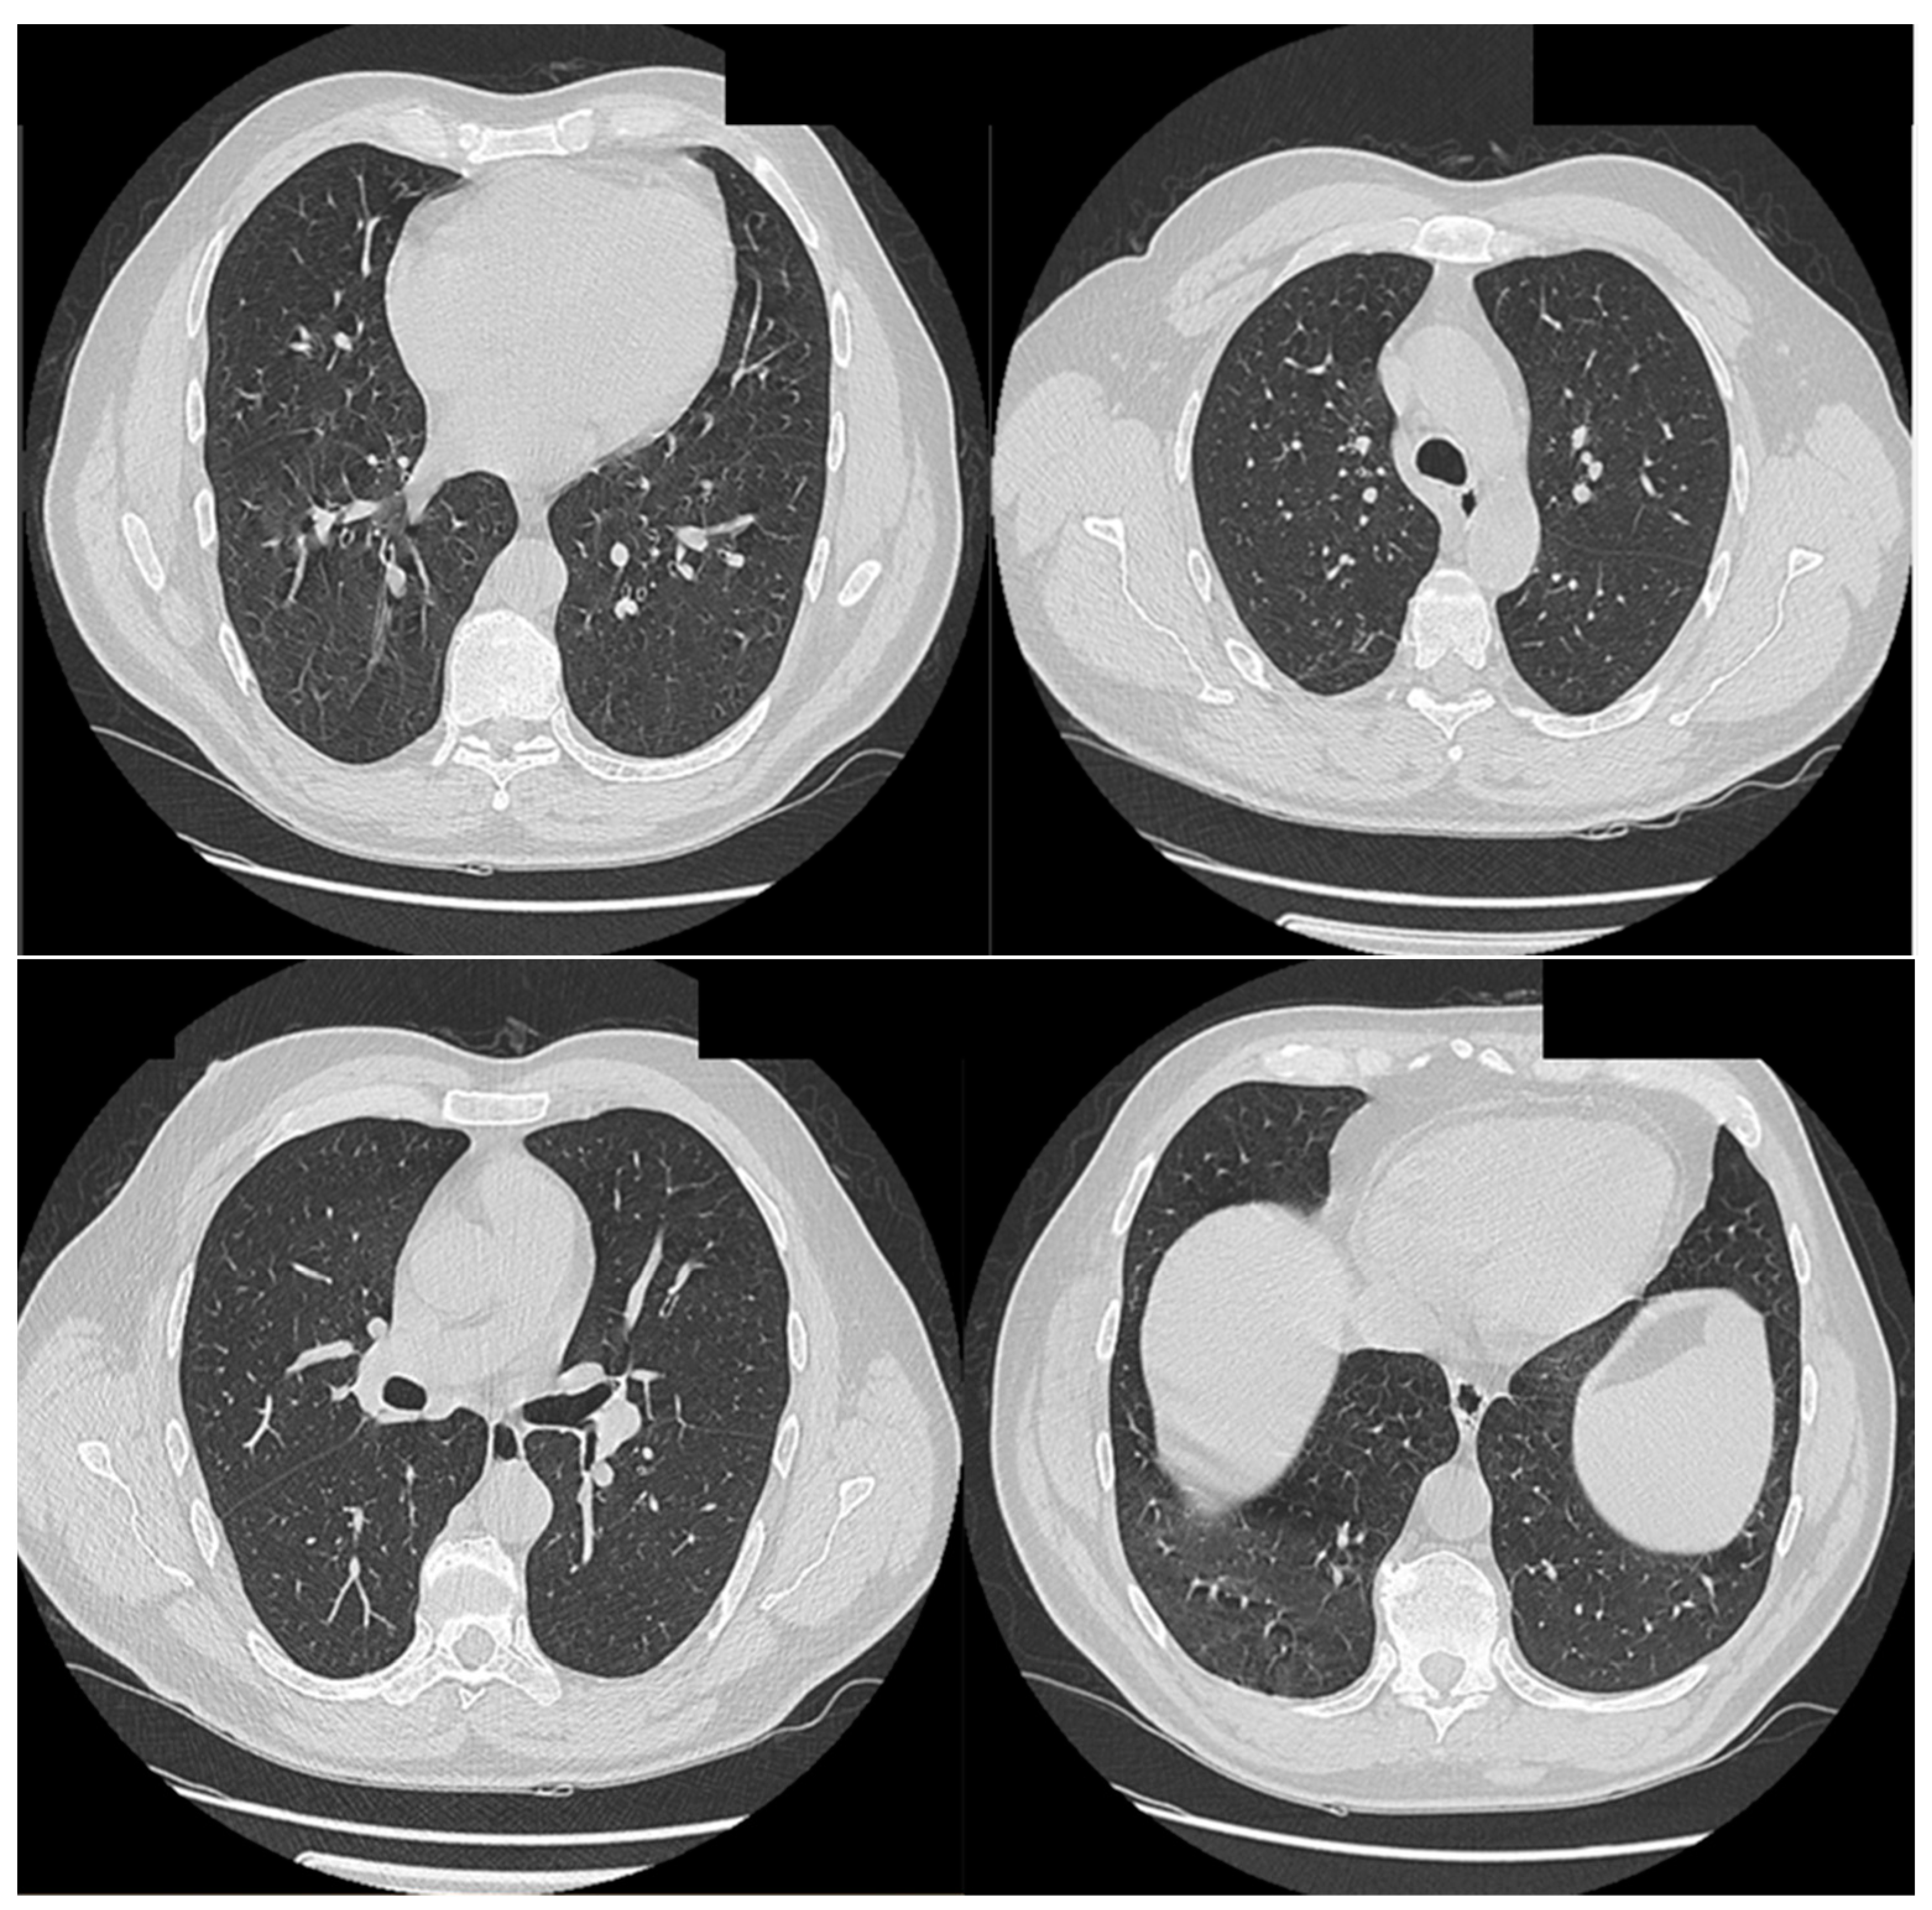

A 50-year-old male patient from a rural area, known to have common B-cell acute lymphoblastic leukemia, was admitted to the Infectious Diseases Department of Bihor County Clinical Hospital, Romania, on 13 August 2022, with a diagnosis of COVID-19 presenting with fever, and received treatment as a result. The patient underwent previous prophylactic antifungal treatment with fluconazole. Chest computed tomography (CT) revealed a fine fibrous band in the right posterior basal region, Figure 1. The paraclinical investigations conducted are presented in Table S1. Treatment was initiated with anti-viral (molnupiravir, for 5 days), corticosteroid (dexamethasone, for 10 days), antibiotics (meropenem, linezolid), for 10 days, platelet transfusion, antipyretics, and antifungal medications (fluconazole) for 14 days.

Figure 1. Thoracic CT (scale bar equals 1.25 mm). Fine fibrous band in the right posterior-basal region.